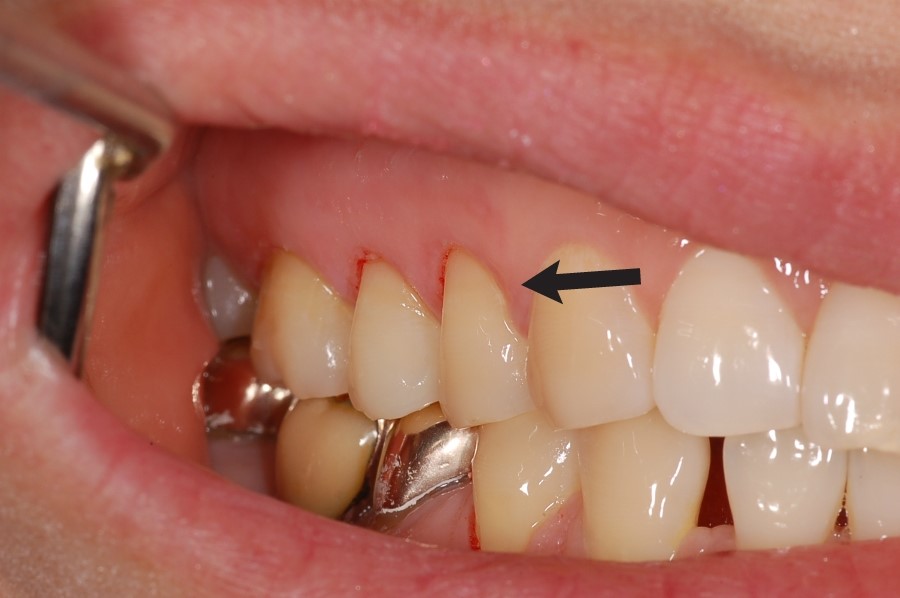

치경부 마모증

After

치아의 치경부(잇몸과 닿아있는 부위)가 칫솔 등에 의해 마모된 경우 치료한 사례입니다.